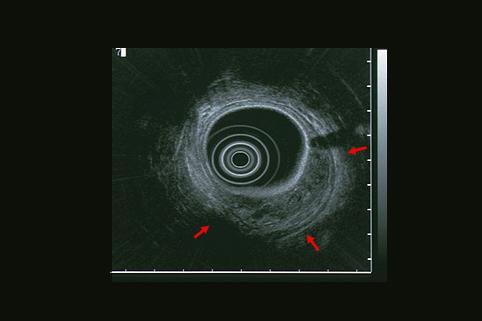

疾病(病理主体)的分类恶性上皮肿瘤/未分化癌

部位(按器官分)大肠/直肠

检查方法超声波

肿瘤的肉眼分类1型(肿瘤型)/

肿瘤最大直径40以上

肿瘤的深度mp